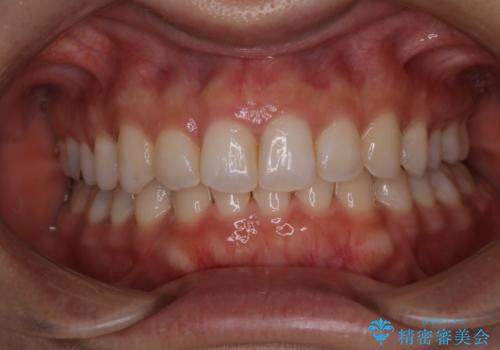

【非抜歯】ガタつきと歯軸を正して長持ちする歯へ

- 歯のガタつきと噛み合わせの改善を主訴に来院されました。

非抜歯で、少量の奥歯の移動と歯列の拡大・IPRを駆使して主訴を改善するための治療計画を立案しました。

非抜歯矯正